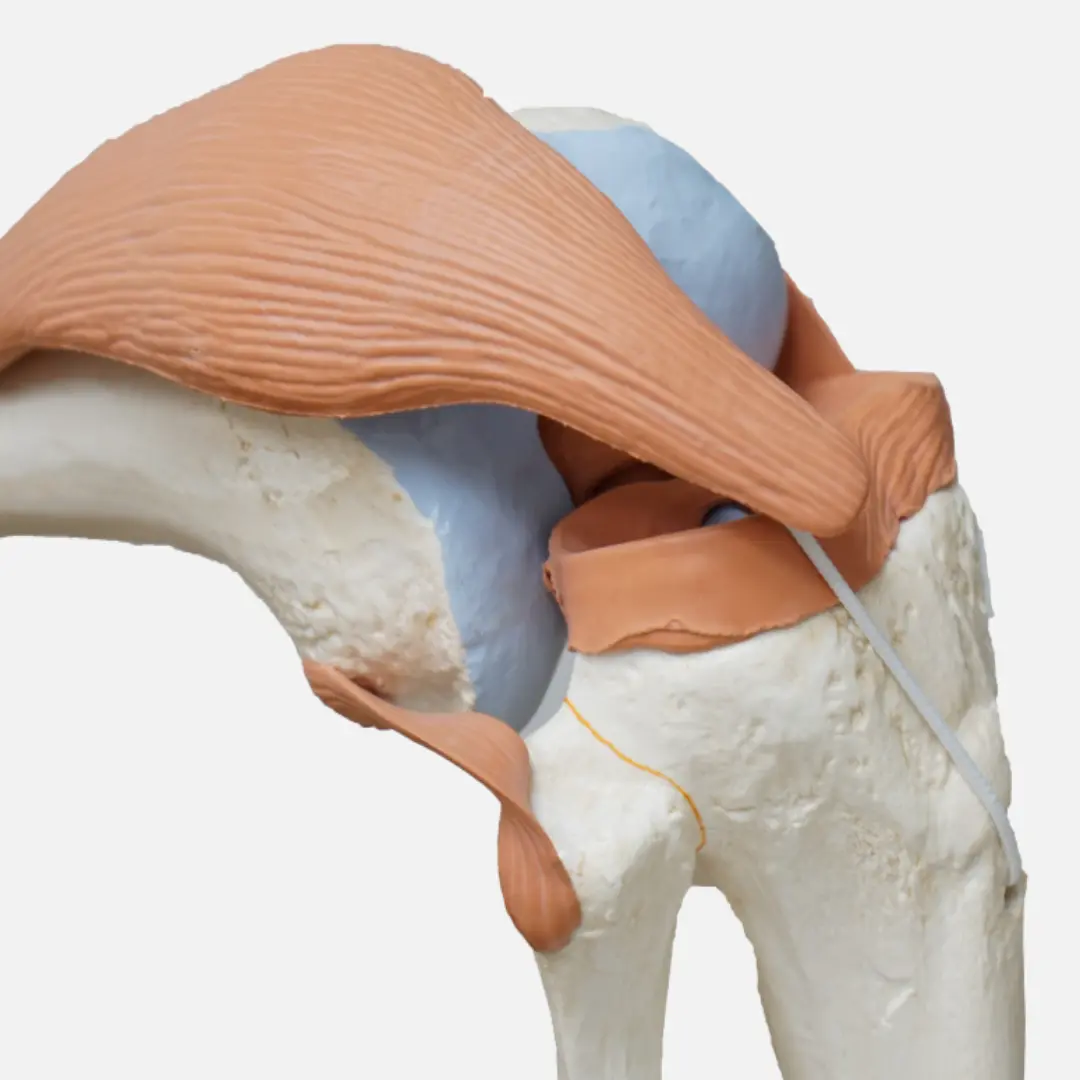

- 십자인대 파열: 무릎의 안정성을 유지하는 십자인대가 손상(부분 또는 완전 파열)되는 경우예요. 주로 운동 중 갑자기 방향을 바꾸거나 넘어질 때 발생하며, '뚝' 하는 소리와 함께 심한 통증과 무릎 불안정성을 유발해요.

- 십자인대 손상 (전방십자인대, 후방십자인대):

- 원인: 무릎에 직접적인 충격이나 갑자기 방향을 바꾸는 동작 등으로 인해 인대가 파열되는 경우예요. 스포츠 활동 중 흔히 발생합니다.

- 증상:

- 손상 시 '뚝'하는 파열음이 들릴 수 있어요.

- 심한 통증과 함께 무릎이 불안정하게 흔들리는 느낌이 들어요.

- 무릎이 붓고 피가 고여 관절 내 출혈이 발생할 수 있습니다.

- 걷거나 서 있을 때 힘이 빠지는 느낌이 들 수 있어요.